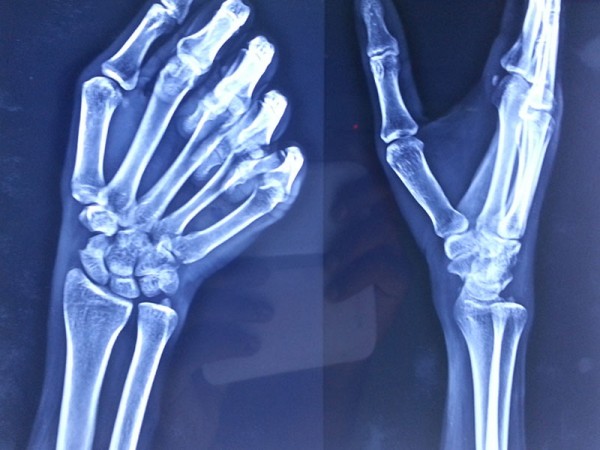

A case of scaphoid non-union

The young, male patient had the fracture of Rt scaphoid/ due to falling on an outstretched hand. The scaphoid fracture was treated, with the plaster cast for 1 ½ month elsewhere. Fracture of Rt Scaphoid was not united. This condition is called, the scaphoid non-union. It was treated with open reduction, and the iliac crest, bone grafting, and K wire stabilization.

After Surgery